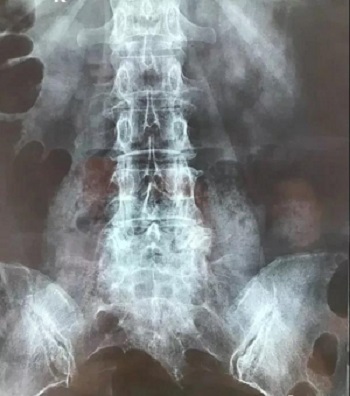

八、拍片子时,如果一张片子上有两张图像的时候,合起来拍一张,分开再各拍一张(如以下三张)